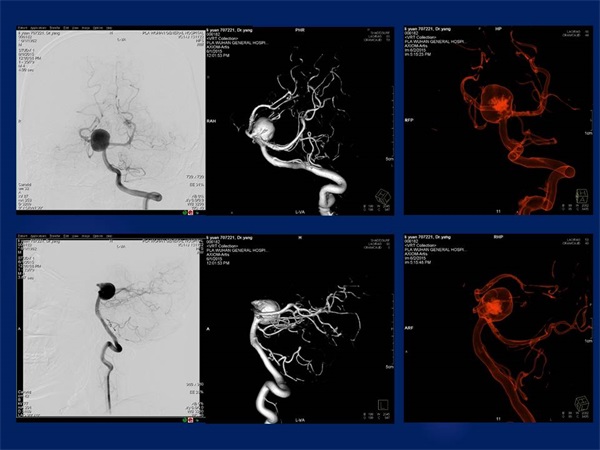

《三维影像融合技术在神经系统疾病诊治与研究中的应用》